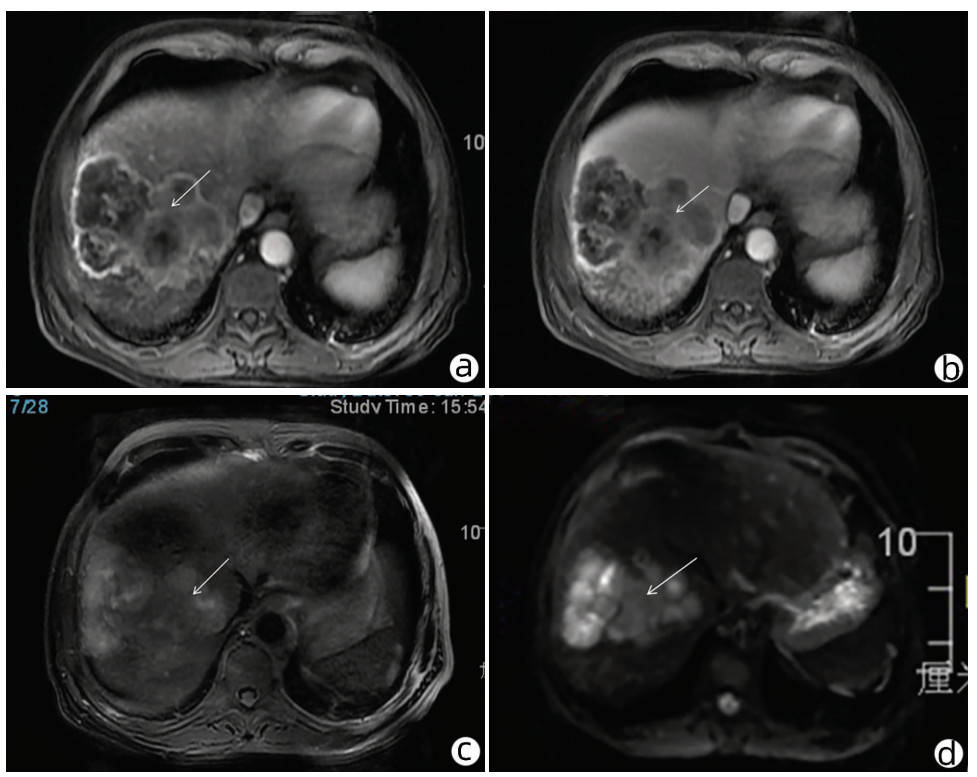

Local embolization combined with targeted comprehensive immunotherapy in treatment of sarcomatoid hepatocellular carcinoma: A case report

Jin LEI, Linzhi ZHANG, Yinying LU, Bowen CHEN, Shi ZUO

2022, 38(4): 880-882. DOI: 10.3969/j.issn.1001-5256.2022.04.026

Abstract(1335) HTML (456) PDF (3487KB)(84)

Abstract: